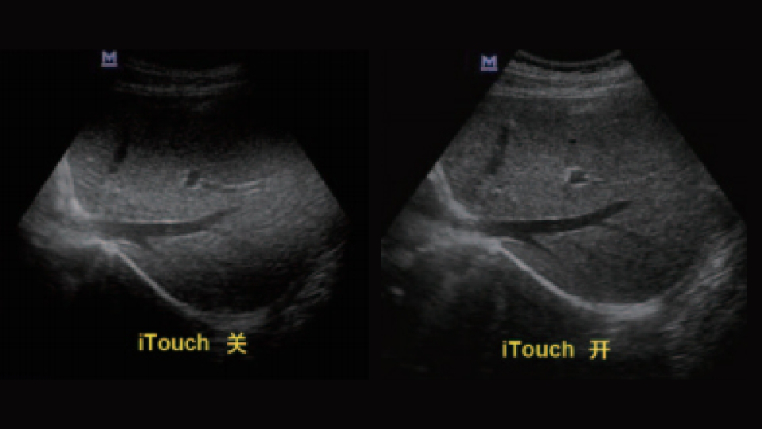

iTouch图像一键优化

集各种模式优化条件于一键,使医生在轻触之间对不同模式下的超声图像进行优化,操作简单快捷